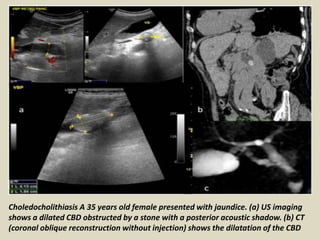

Choledocholithiasis A 35 years old female presented with jaundice. (a) US imaging

shows a dilated CBD obstructed by a stone with a posterior acoustic shadow. (b) CT

(coronal oblique reconstruction without injection) shows the dilatation of the CBD